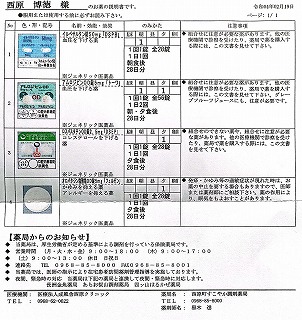

2021.11.13より 西原クリニック 0968-62-0622

2021.12.04 西原クリニック処方箋=pdf

2021.11.13